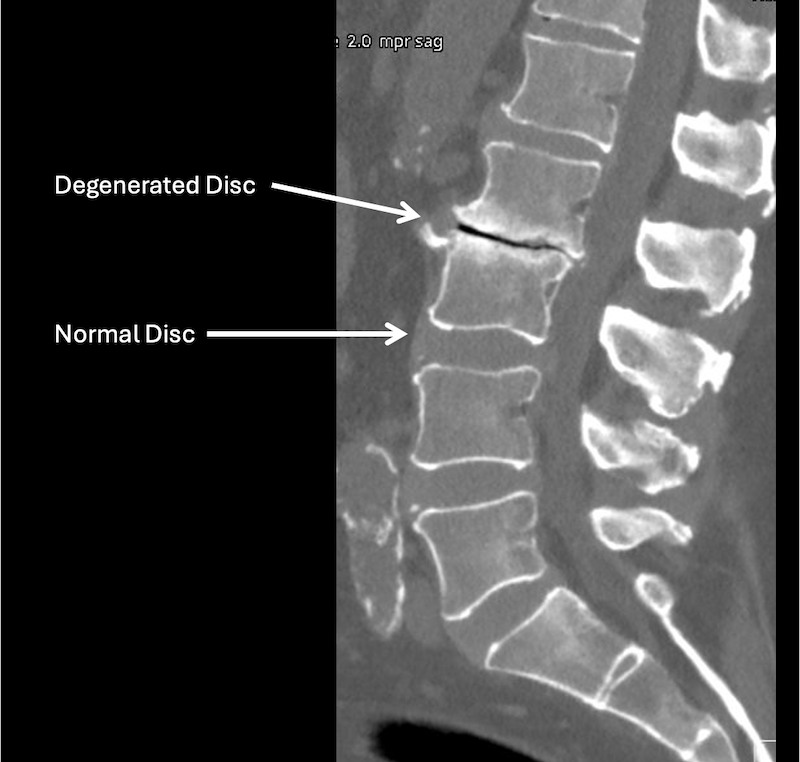

A lumbar spine X-ray showing a normal disc and a degenerated disc with labels pointing to each.

• Not always. MRI is usually recommended when symptoms persist or worsen.

• X‑rays can show certain changes such as disc height loss, and bone spur formation. They do not show nerves.

However, X-rays are also important because they can show your bone alignment and possibly other issues that are not shown on MRI.

• Not always. Imaging findings and symptoms do not always match.